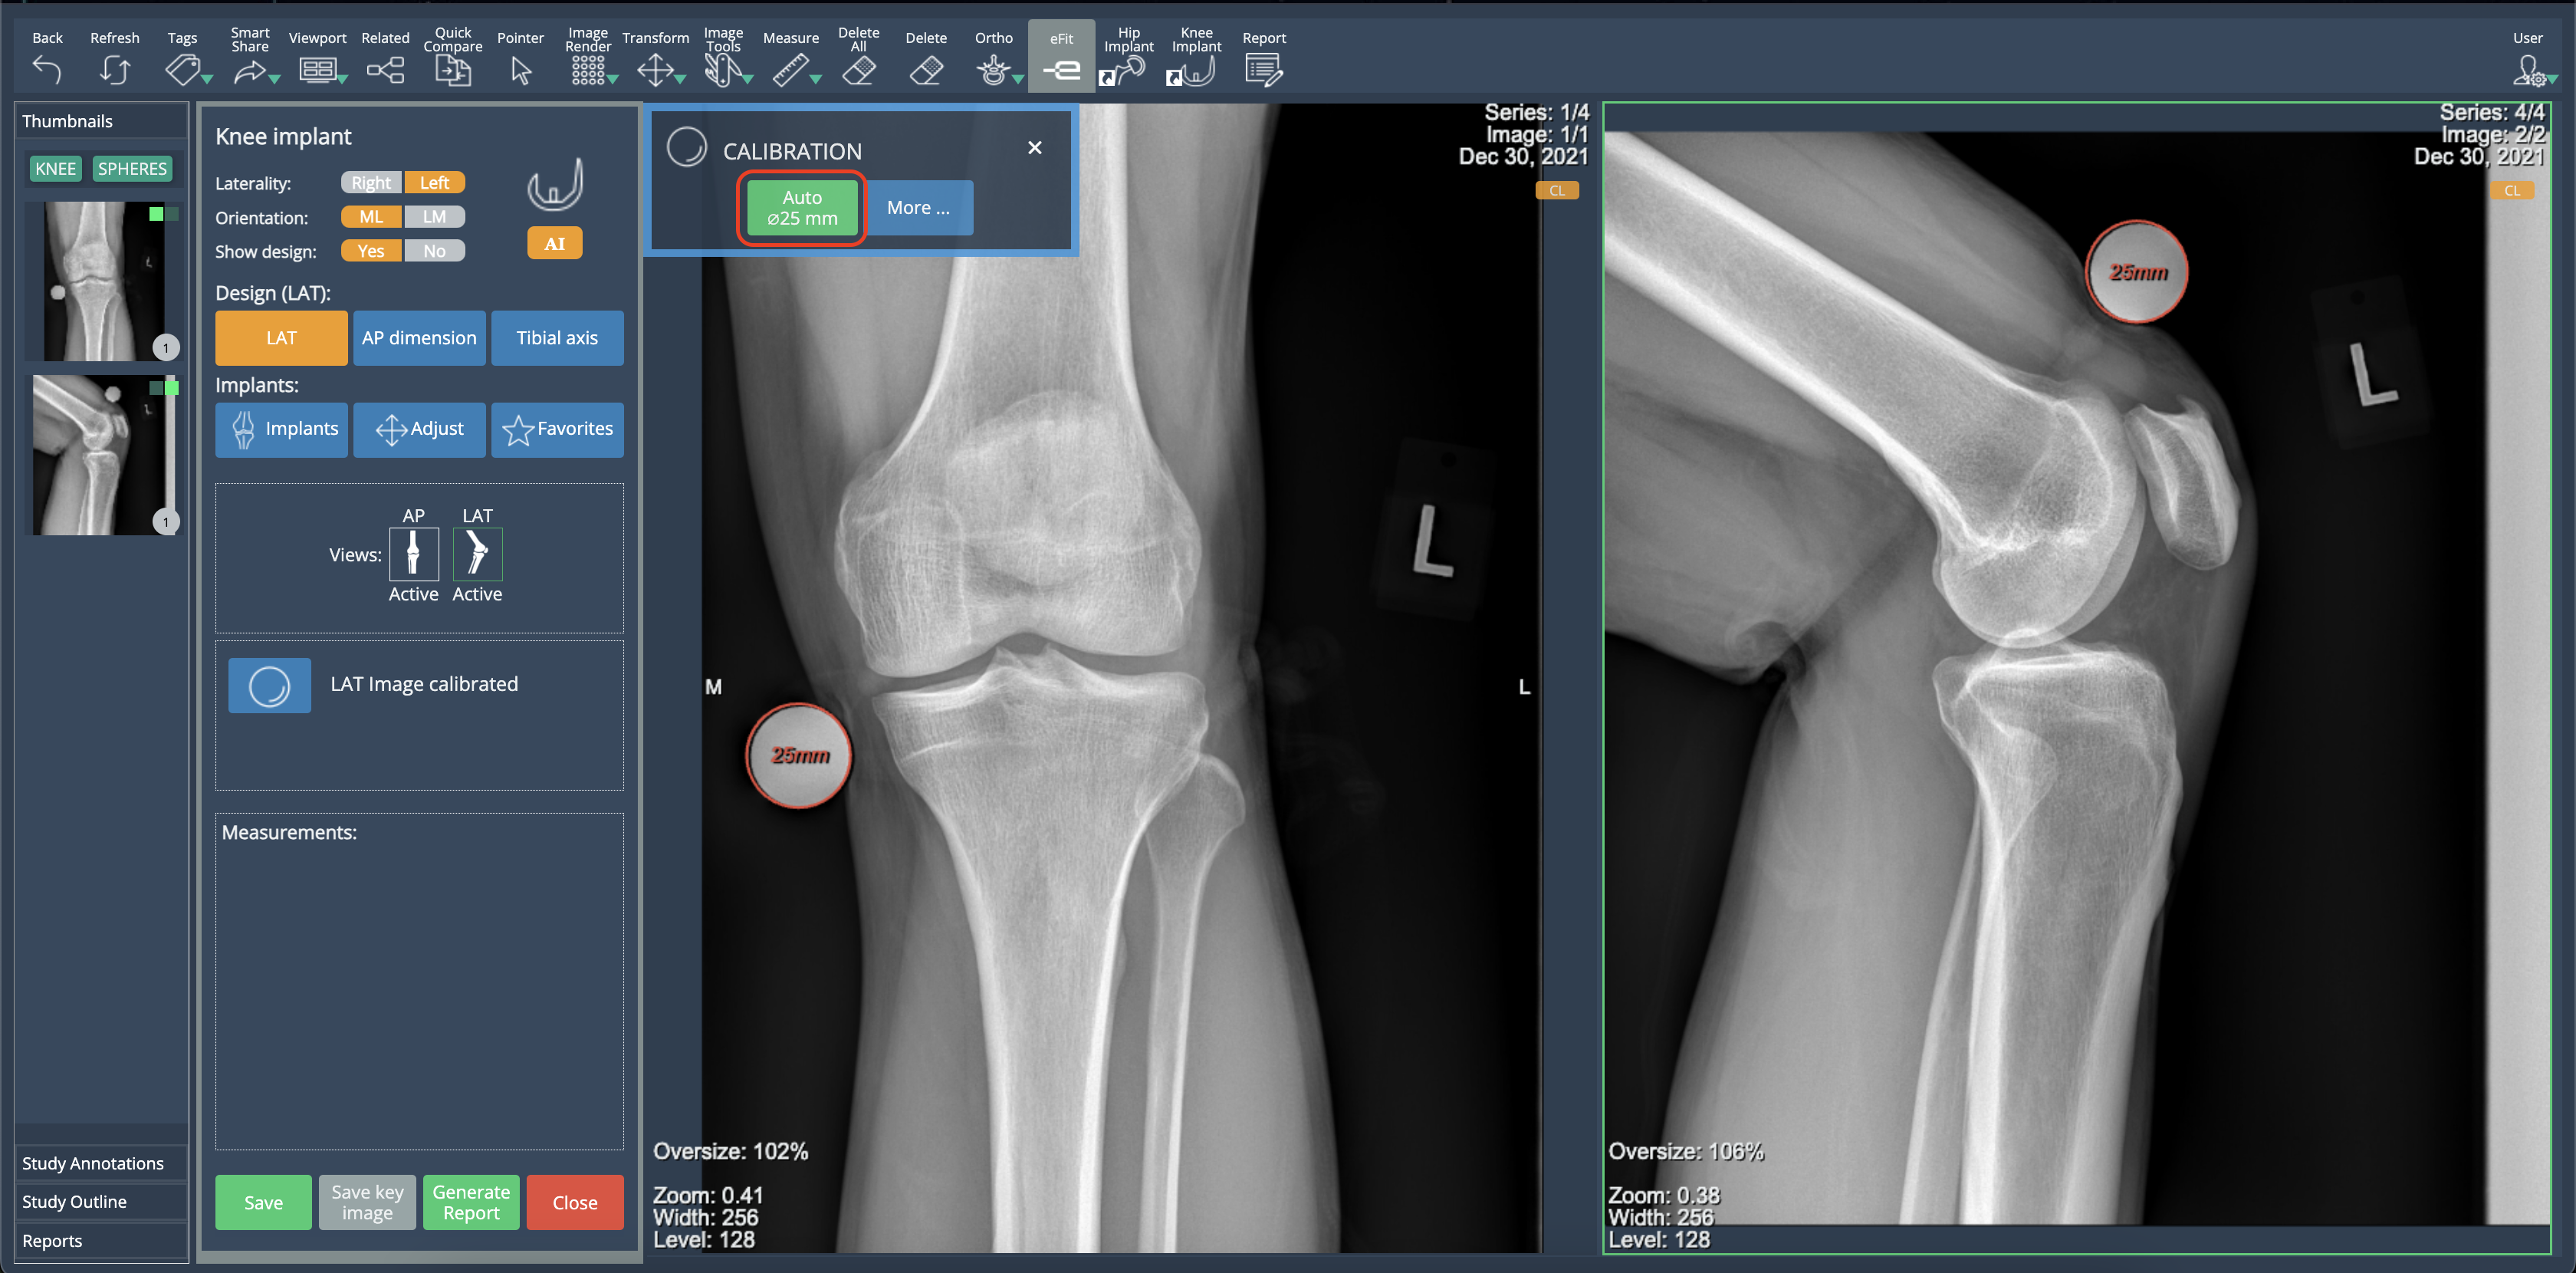

Improved Auto-Calibration for Knee Templates

Auto-calibration now applies to both knee views simultaneously, improving efficiency and reducing manual steps. Previously, users had to run the auto-calibration separately for each view. With this update, the process is executed for both views at once, streamlining workflow.